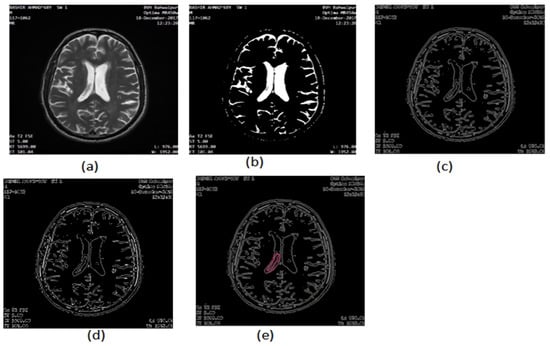

2.2.7. Area Segmentation using Watershed Algorithm

2.2.8. Region Masking and the Separation

2.3. Proposed a Colorized Method for Masked Area Colorization